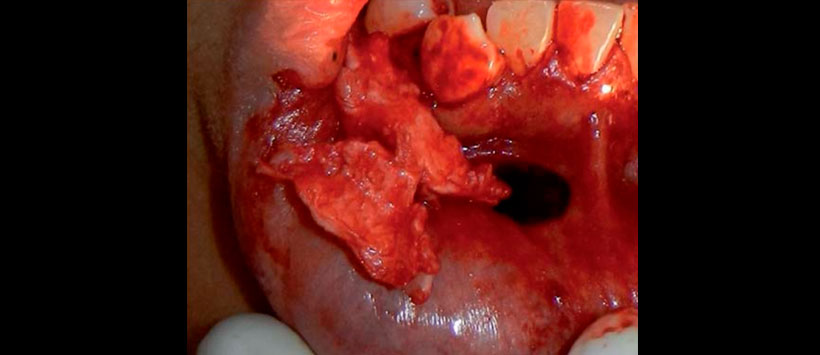

Se procede a realizar incisión lineal en la región vestibular mentoniana derecha, para disecar subperiósticamente hasta encontrar tejido óseo, mismo que se encuentra adelgazado y crepitante durante la palpación. Se realiza osteotomía de la zona para tomar biopsia incisional de la lesión quística, misma que presenta una consistencia firme, de color blanco con zonas café claro, y fácilmente desprendible (Figura 3).